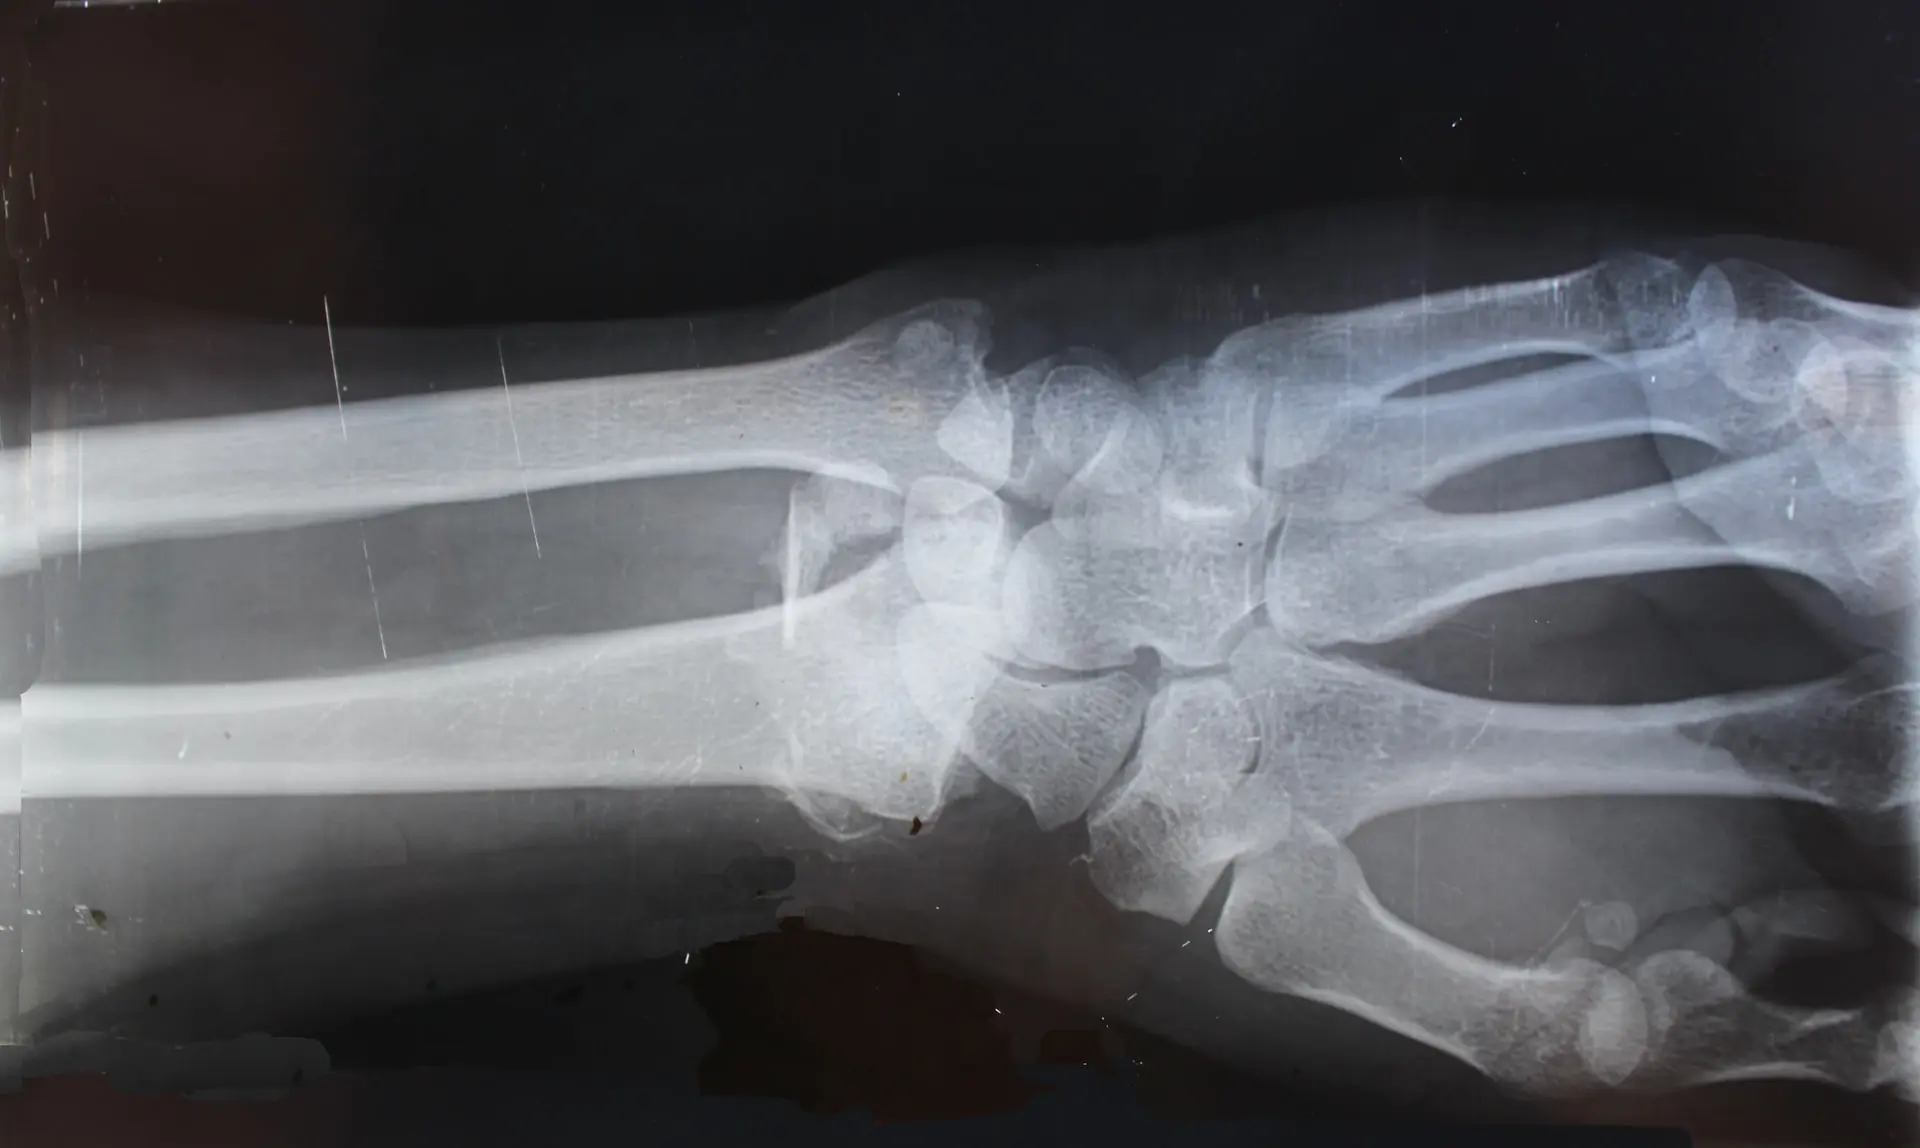

Jakie badania zaleca reumatolog?

Lekarz może także zalecić ogólną morfologię krwi, badania moczu, USG wybranych stawów lub tomografię komputerową. Komplet badań wraz z wywiadem, który lekarz przeprowadza z pacjentem, stanowią podstawę do dobrania odpowiedniego leczenia.